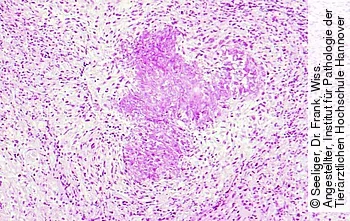

Histologisch ist die namensgebende Eosinophilie betroffener Gewebe nachzuweisen. Aufgrund der Degranulation eosinophiler Granulozyten kommt es zu granulomatösen oder ulzerativen Reaktionen des umgebenden Gewebes. Neben eosinophilen Granulozyten finden sich vor allem Makrophagen und Lymphozyten. In der Nachbarschaft befindliche kollagene Fasern werden von den entzündlichen Veränderungen mitbetroffen [Abb. 4].